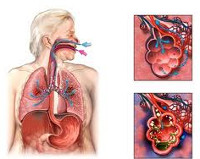

Аспирацио́нная пневмони́я (лат. aspirātiō — «вдыхание») — воспаление лёгких, возникающее при вдыхании или пассивном попадании в лёгкие различных веществ в массивном объёме, чаще всего в практике — рвотных масс. Воспаление возникает через специфические свойства субстанций, вызывающих сильные воспалительные реакции.

К аспирационной пневмонии часто приводит регургитация (затекание) желудочного содержимого в дыхательные пути при кардиопульмональной реанимации, шоке, нарушениях сознания (в том числе, алкогольной и героиновой интоксикации), при нарушении глотания в рамках различных неврологических заболеваний (бульбарный паралич, псевдобульбарный, миастения, постравматическая энцефалопатия, тяжело протекающие нейродегенеративные заболевания, ассоциированные с нарушением нервно мышечной проводимости, запущенные менингиты, миастении дисфагии), заболеваний пищевода (ГЭРБ, рак пищевода, грыжа пищеводного отверстия и диафрагмы), тяжело протекающие уремические энцефалопатии, диабетические полиневриты. Соляная кислота содержимого желудка с низким pH (<2,5) является очень агрессивной по отношению к эпителию дыхательных путей, вызывая химический пневмонит. Данный тип поражения приводит к спазму бронхов, ателектазам, бронхоэктазам, абцессам, гангренам легких, буллюсу, альвеолиту, стридору, нарушая барьер слизистой и открывая «ворота» для инфекций. Отдельно выделяют синдром Мендельсона — аспирационную пневмонию, вызванную аспирацией желудочного содержимого у больных под наркозом[1]. Данный синдром может осложниться отеком легких и сердечно-лёгочной недостаточностью.

Сценарий развертывания событий при аспирации содержимого в трахеобронхиальное дерево может варьировать от полного отсутствия нарушений до развития респираторного дистресс-синдрома, дыхательной недостаточности и гибели пациента. Условиями, приводящими к развитию аспирационной пневмонии, служат нарушения факторов местной защиты в дыхательных путях и патологический характер аспирационных масс (количество, химические свойства и рН, степень инфицированности и пр.). Основными патогенетическими звеньями, приводящими к возникновению аспирационной пневмонии, выступают механическая обструкция дыхательных путей, острый химический пневмонит и бактериальная пневмония.

При вдыхании большого объема аспирата или крупных твердых частиц возникает механическая обструкция трахеобронхиального дерева. Возникающий при этом защитный кашлевой рефлекс способствует еще более глубокому проникновению аспирированного субстрата в бронхи и бронхиолы, что может привести к развитию отека легких. Механическая обструкция сопровождается развитием ателектазов легкого и застоем бронхиального секрета, на фоне которых увеличивается риск инфицирования легочной паренхимы.

В ответ на агрессивное воздействие аспирированного содержимого развивается острый химический пневмонит, характеризующийся выбросом биологически активных веществ, активацией системы комплемента, высвобождением факторов некроза опухолей, цитокинов и т. д. Дальнейшие патологические изменения в легочной паренхиме обусловлены ее повреждением биологически активными веществами, а не прямым действием аспирата. На фоне рефлекторного бронхоспазма, ателектаза части легкого, снижения легочной перфузии и прямого повреждения альвеол быстро развивается гипоксемия. С присоединением бактериального компонента нарастает дыхательная недостаточность, лихорадка, кашель, т. е. появляются все признаки бактериальной пневмонии. В этой стадии аспирационной пневмонии рентгенологически определяются очаги инфильтрации, нередко возникают легочные абсцессы и эмпиема плевры.